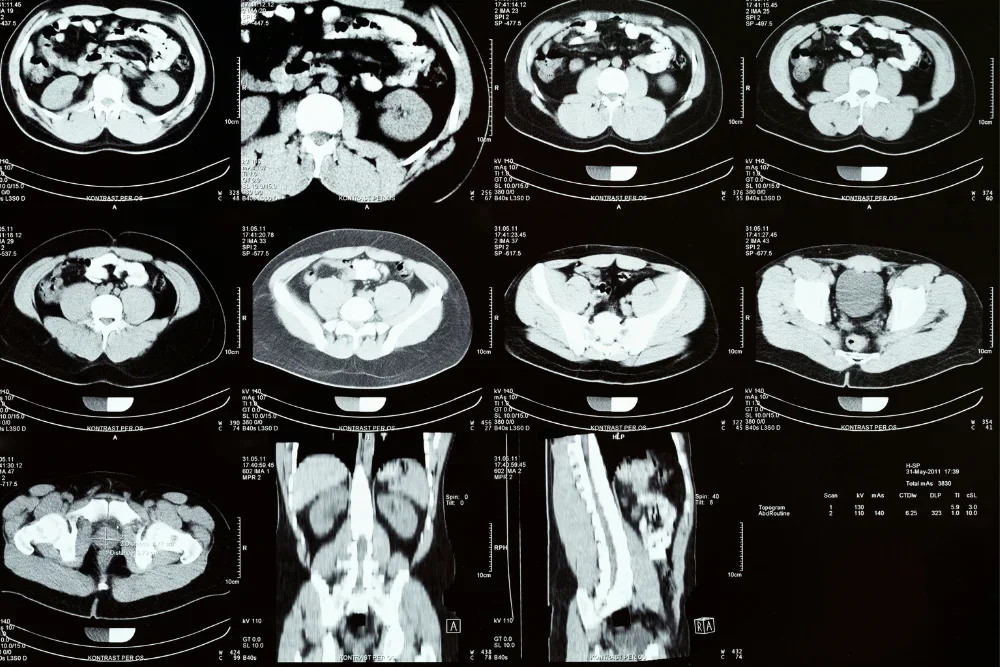

La tomografía de vías urinarias es un procedimiento médico no invasivo que utiliza rayos X para obtener imágenes detalladas de los órganos urinarios y de los tejidos que los rodean, permitiendo a nuestros especialistas evaluar y diagnosticar posibles afecciones.